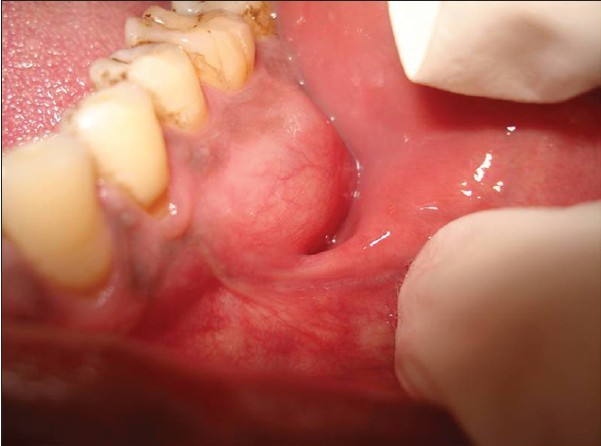

Ameloblastoma is a rare odontogenic tumor, which means it's formed from the normal tissues found in the mouth. Their location is predominately the lower jaw, also known as the mandible. Still, they can be found in the upper jaw or maxilla as well. Sometimes, ameloblastomas are located in the soft tissues surrounding the jaws. There is no known cause for this kind of tumor. However, it may be associated with impacted third molars. Ameloblastomas are usually noncancerous (benign), and they generally affect people between 40 and 60 years old.

Ameloblastoma is usually painless, with the only symptom being swelling in the area. It is usually only identified on radiographic examination in a dental office. Early developing lesions do not displace teeth or cause numbness, so the patient may not know a tumor is growing in one of their jawbones. If a potential lesion is identified on a dental radiograph, more elaborate imaging is required. This will include a CAT scan and possibly an MRI. However, the diagnosis cannot be solely determined by imaging. It requires a biopsy to make the final diagnosis. Cysts will sometimes appear similar to the ameloblastoma on the imaging.